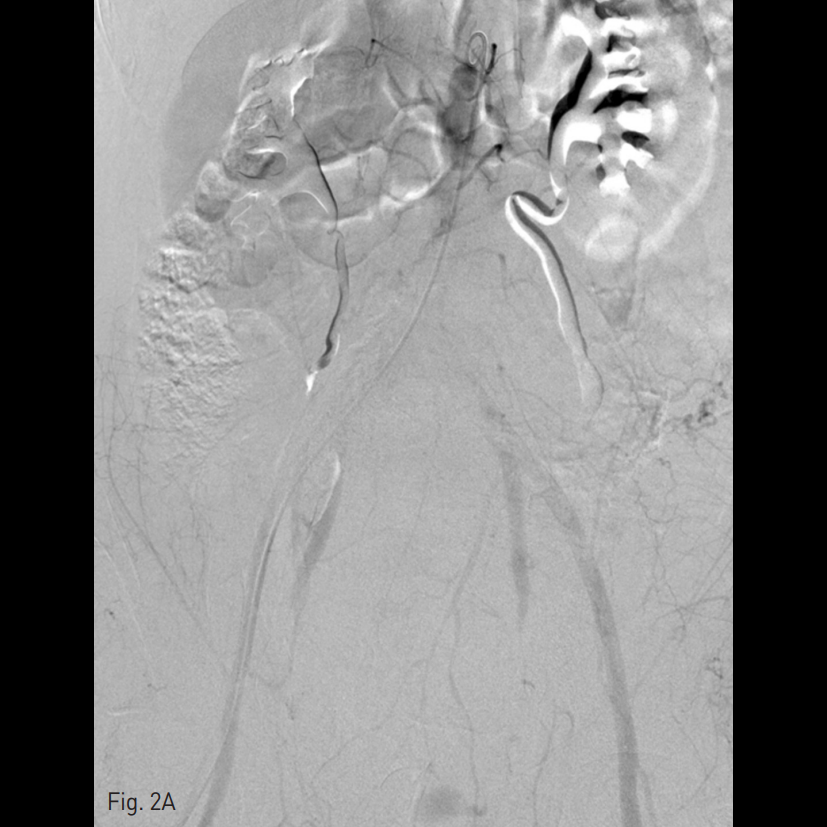

양측 내측 장골동맥을 선택하여 시행한 혈관조영술에서 양측 자궁 동맥이 심하게 비후되어 있으며, 출혈의심 소견이 보였다. 양측 외측 장골동맥 의 가지에서는 출혈 의심소견이 없었다. 대동맥 조영술에서는 하장간막동맥으로부터 출혈 소견이 보였다.

우측 총대퇴동맥을 천자하여 5 Fr sheath를 삽입하고, 5 Fr RUC catheter (Roberts Uterine Catheter, COOK medical, Bloomington, IN, USA)를 이용하여 좌측 내측 장골동맥을 선택하여 조영술을 시행한 뒤 좌측 자궁동맥을 선택하여 조영술 시행하였으며 (Fig. 1A), 출혈의심소견이 있어 gelfoam을 이용하여 색전술을 시행하였다 (Fig. 1B). 이후에 시행한 우측 내측 장골동맥을 선택하여 조영술을 시행한 뒤 (Fig. 1C), 우측 자궁동맥을 초선택하여 조영술을 시행하였을 때, 우측 자궁동맥이 비후되어 있어, gelfoam을 이용하여 색전술을 시행하였다. 색전술 직후 산부인과 진찰에서 지속적인 출혈소견이 보였다. 이에 5 Fr pigtail catheter를 이용하여, 대동맥 조영술을 시행하였다. 하장간막동맥 (Inferior mesenteric artery)으로 부터 출혈 소견이 관찰되었다 (Fig. 2A). 이에 대해서 2.2 Fr 마이크로카테터 (Progreat, Terumo, Japan)를 이용하여 하장간막동맥을 초선택하여 코일(Nester microcoil, COOK Medical, Bloomington, IN, USA)과 gelfoam (Spongostan, Ferrosan Medical Devices, Denmark)을 이용하여 색전술을 시행하였다 (Fig. 2B). 이후 다시 하장간막동맥 조영술을 시행하여 더 이상의 출혈이 없음을 확인하고 시술을 종료하였다 (Fig. 2C).

Fig. 2

A. Aortogram revealed active extravasation of contrast media from the distal branch of the IMA.

B. Active bleeding was better visualized on angiogram using 2Fr microca theter.